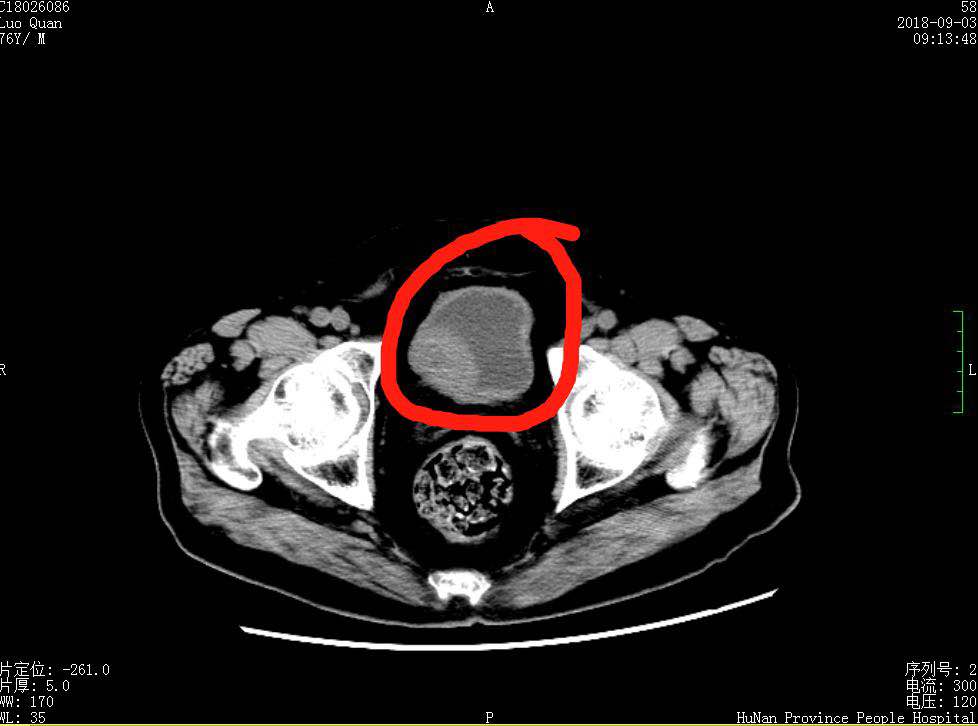

是什么使老人如此感激?原来,“闯”入的这位年近8旬的罗老是位集荣誉与成就于一身的高级烹饪大师、“国家首批特级厨师”、“南粤湘菜第一人”,2007年被湖南省政府授予:“中国湘菜大师”,是湘菜的领军人物,桃李满天下。今年8月31日,因反复血尿1年、排尿困难伴尿不尽2年,罗老入住到捷克论坛 泌尿四科。经检查诊断为“膀胱肿瘤”。B超及CT检查显示罗老膀胱内有一4.0*2.8肿瘤,如此大的肿瘤,需要做膀胱全切。以杨科主任为首的手术团队考虑到患者的生存质量及患者的要求,经过精心设计手术方案和完善的术前准备,于9月12日在腰硬联合麻醉下亲自为罗老作了“经尿道钬激光膀胱肿块剜除术”,保留了罗老的膀胱,避免了他终身要带着尿造口袋的痛苦和尴尬。术后经治疗护理,规范化疗,病情好转出院。